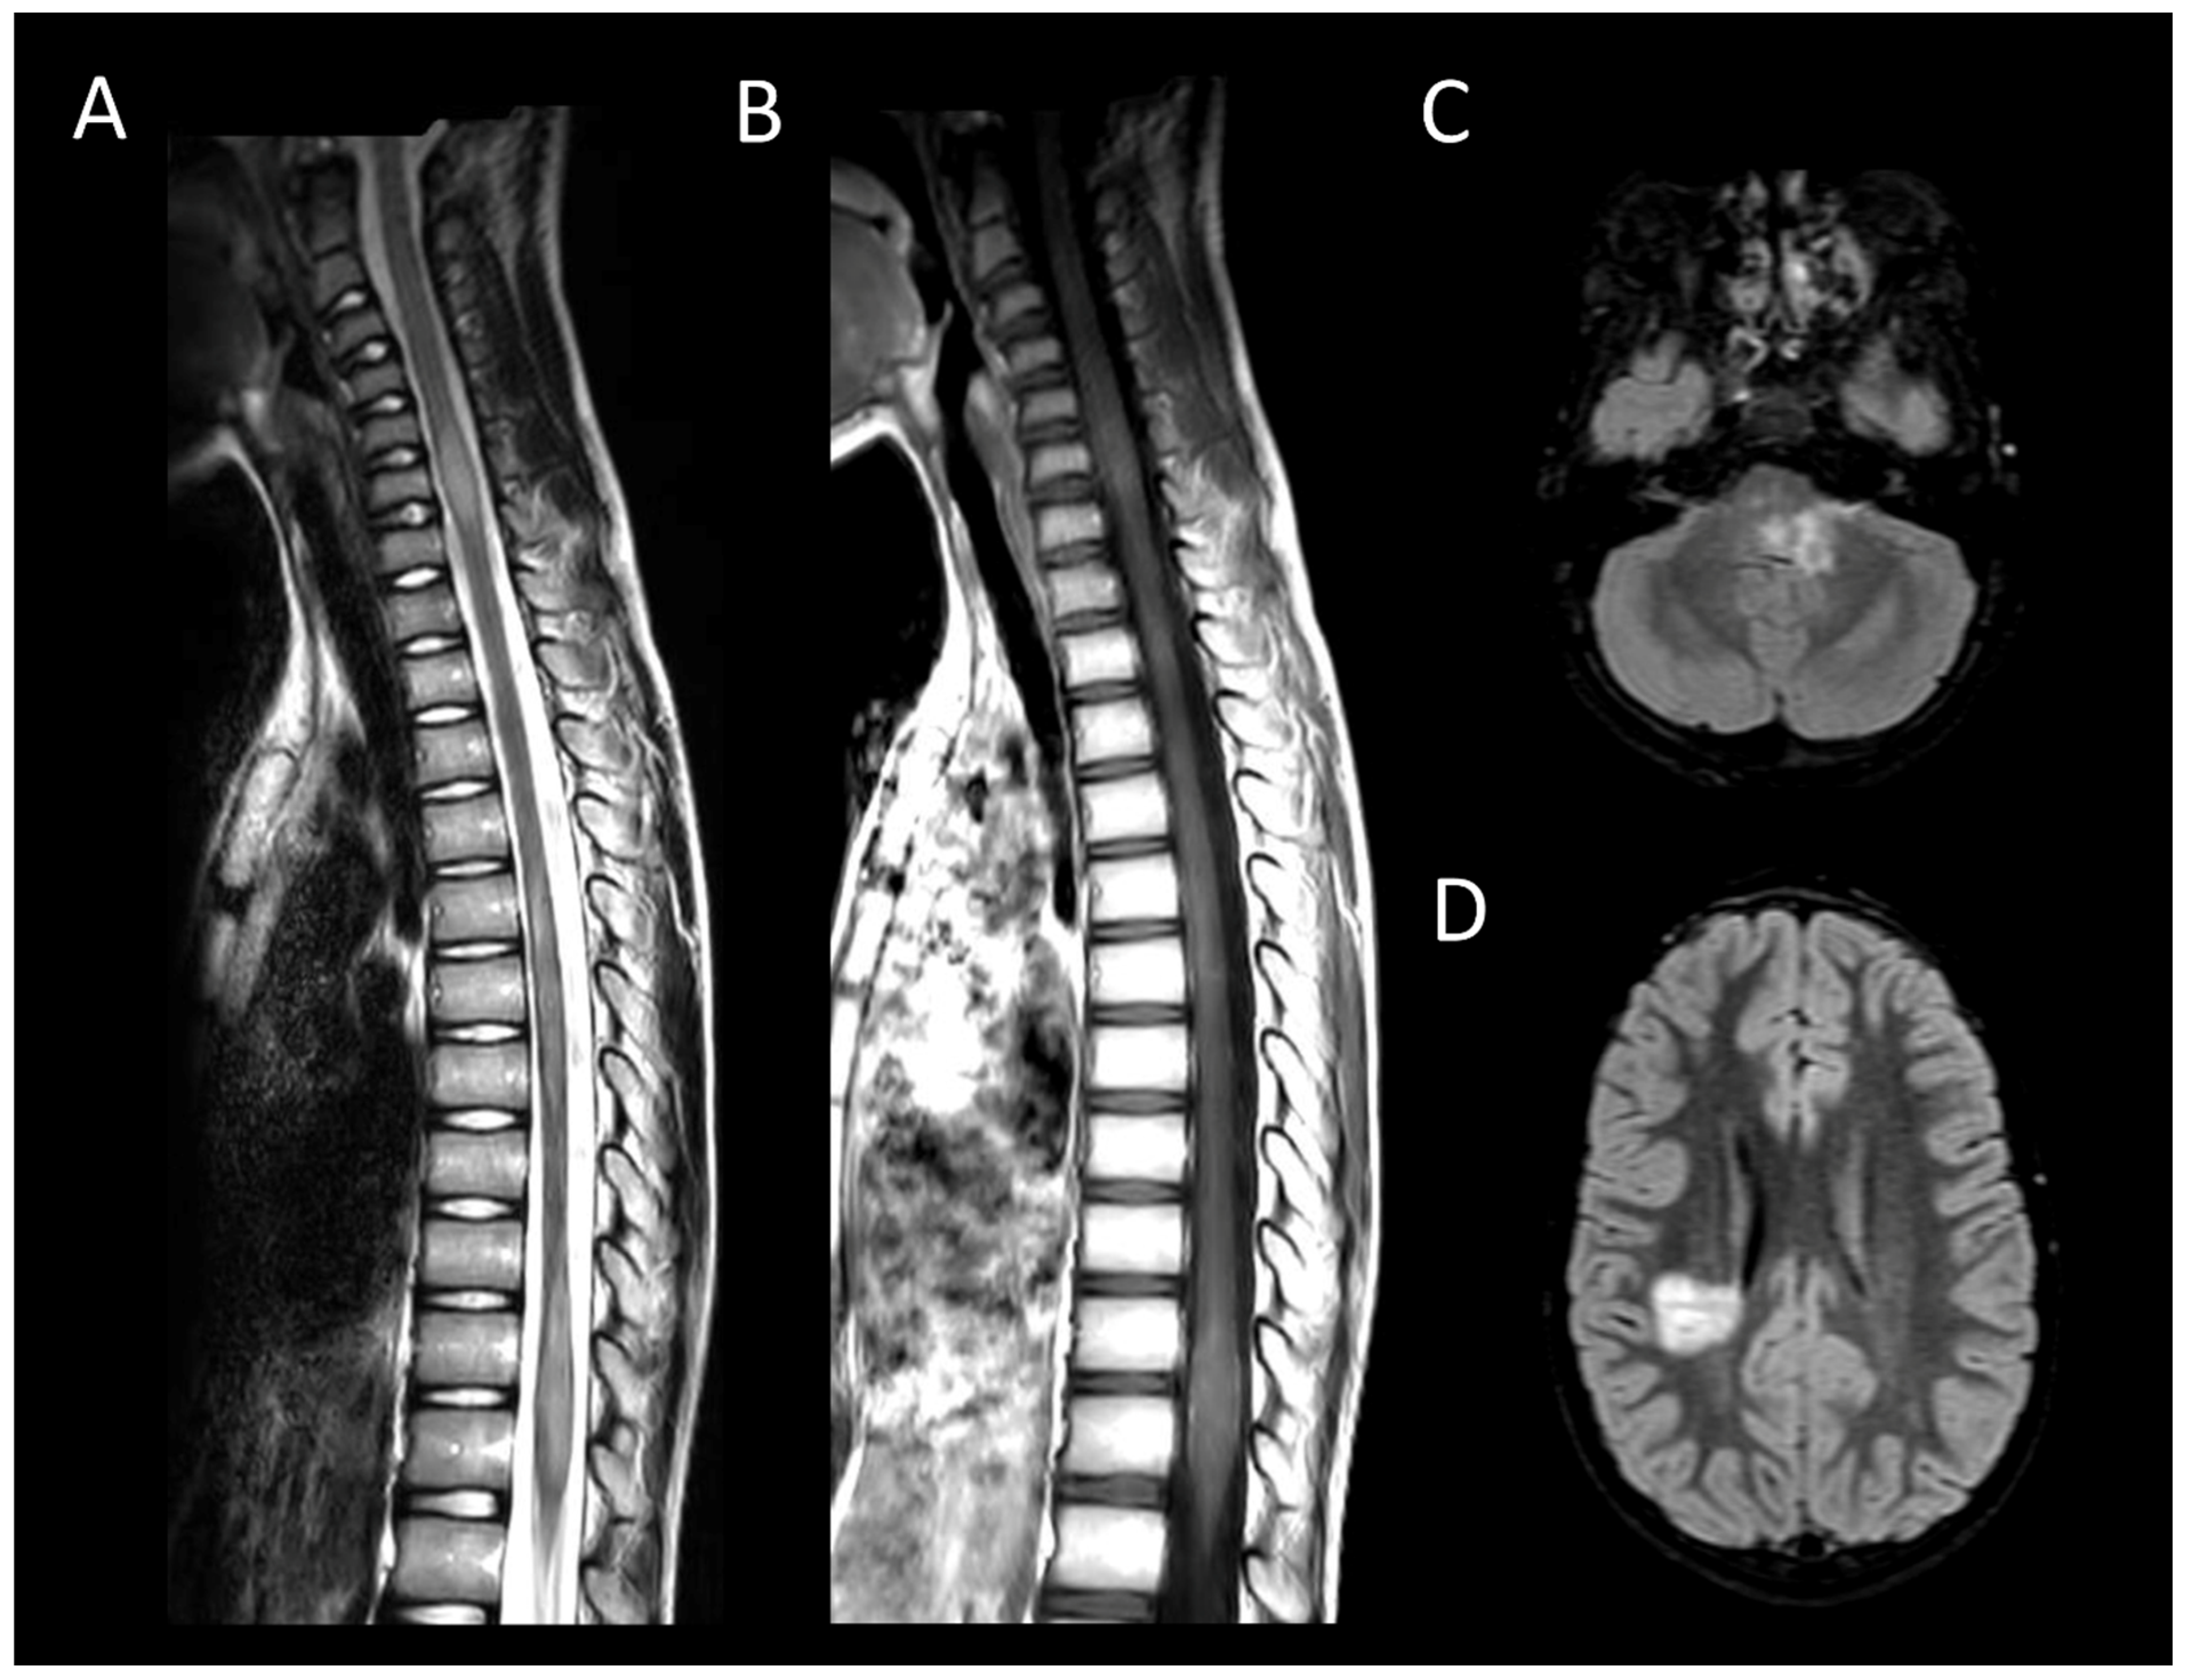

3.3.1. Spinal Cord Infarction

3.3.2. Spinal Dural Arteriovenous Fistula

3.3.3. Spinal Cavernous Malformation

3.3.4. Hematomyelia

3.5. Metabolic and Toxic Myelopathies

Subacute Combined Degeneration of the Spinal Cord and Mimics